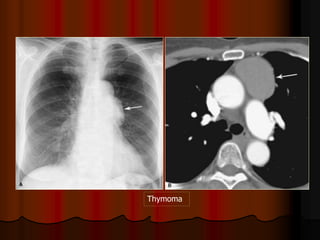

HILUM OVERLAY SIGN: TERATOMA

Thymoma